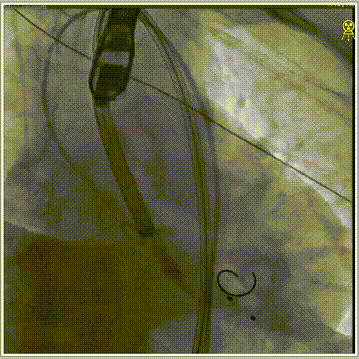

经左股动脉穿刺,置入6F股动脉穿刺鞘,将猪尾导管引导至主动脉根部,行主动脉造影。180bpm下置入23mm球囊扩张,沿导丝送入美敦力Evolut PRO经导管主动脉瓣膜系统,采用美敦力独有的commissual alignment技术,最大程度保护冠脉。递送系统顺利送入动脉系统并顺利过弓跨瓣,在采用世界先进的Cusp Overlap技术植入技术,最终目标位置完美释放,瓣膜立即工作,展开形态良好,无瓣周漏,无冠脉阻挡,无传导阻滞发生,术后无压差,血液动力学稳定,手术圆满成功。